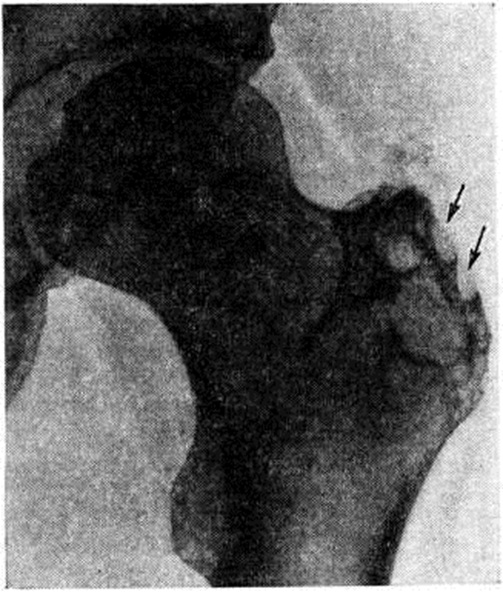

Рентгенограмма левого тазобедренного сустава при туберкулёзном трохантерите: верхненаружный отдел большого вертела разрушен, поверхность вертела неровная с глубокими узурами (указаны стрелками).

Туберкулёзный очаг вначале располагается в толще большого вертела, чаще у его наружной поверхности (рисунок), поэтому воспаление быстро распространяется в мягкие ткани и осложняется натечным абсцессом (смотри полный свод знаний: Натечник) или свищом. Свищи (смотри полный свод знаний) обычно короткие, прямые, но могут распространяться вдоль мышц бедра, становясь извилистыми и длинными, открываясь на задней и боковой поверхностях бедра. В таких случаях показано рентгеноконтрастное исследование — абсцессография (смотри полный свод знаний) и фистулография (смотри полный свод знаний). При этом может быть установлена связь мягкотканного воспалительного очага с первичным костным очагом, выявлена разветвленная сеть свищевых ходов, наличие затеков. Очаг деструкции в большом вертеле обычно имеет размеры от 4—5 миллиметров до нескольких сантиметров в диаметре, контуры его неровные, нечеткие, кость вокруг очага порозна, если нет свищей. Свищевые формы обычно осложняются вторичной инфекцией, что приводит к образованию зоны диффузного остеосклероза вокруг очага деструкции. Постепенно деструктивные изменения нарастают, процесс распространяется как в глубь большого вертела, так и по поверхности, в краевых отделах появляются секвестры диаметром не более 1 сантиметров, имеющие, как правило, большую плотность по сравнению с сохраненной костной тканью.